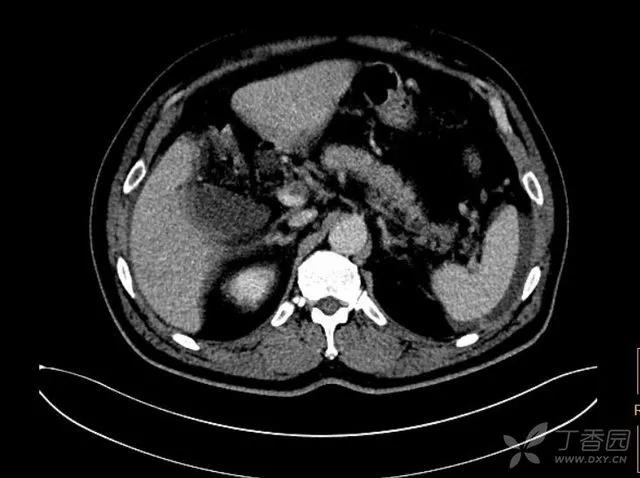

急诊平扫 CT:

看看增强 CT 图片,能发现问题吗?

动脉期:

门静脉期: